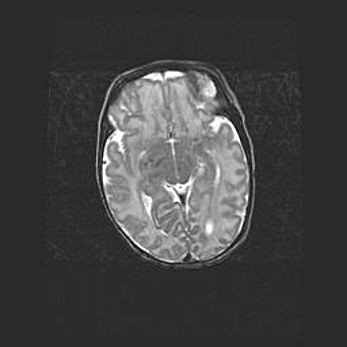

Неполная лизэнцефалия (пахигирия). Открытая гидроцефалия.

Возраст: 17 дней

Вес: 3110 г

Пол: мужской

Окружность головы: 33,5 см

Срок гестации: 35-36 недель

Лизэнцефалия—недоразвитие корковой пластинки и мозговых извилин в результате нарушения миграции нейронов коры. Поверхность мозговых полушарий гладкая. Микроскопически выявляется отсутствие нормальных слоев коры и скопление групп нейронов в подкорковом белом веществе.

Пахигирия—уменьшение числа вторичных извилин. В пораженном полушарии нервные клетки образуют толстый недифференцированный слой с неправильно расположенными нервными волокнами и группами гетеротопных клеток. Нервные клетки незрелые. Белое вещество истончено. При этом нередко аномально развит корково-спинномозговой путь.